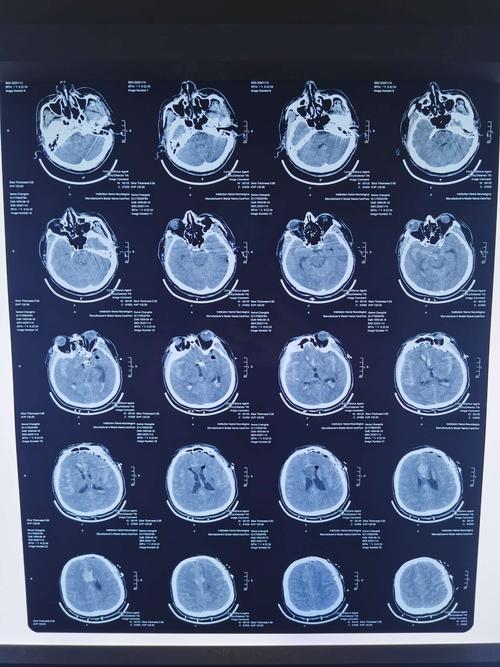

蛛网膜下腔出血图片,蛛网膜下腔出血ct

蛛网膜下腔出血ct

蛛网膜下腔出血ct表现

蛛网膜下腔出血ct解读

蛛网膜下腔出血影像图

蛛网膜下腔出血ct图解